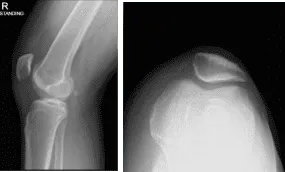

Ha estado quejándose de dolor de rodilla a pesar de un manejo conservador en forma de fisioterapia y medicamentos antiinflamatorios. El paciente presentó una radiografía de la rodilla derecha que no mostró cambios degenerativos significativos. No hay fracturas.

Radiografía de la rodilla derecha con rótula